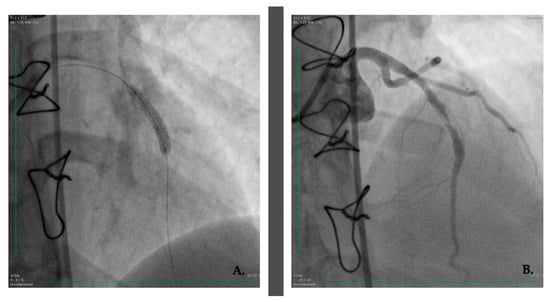

2. Case Presentation